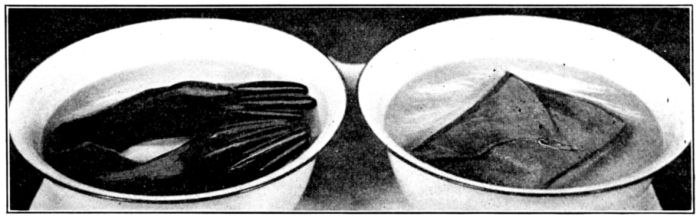

| 42. | Gloves, ready for dry sterilization | 160 |

| 76. | Wrong and right methods of boiling gloves | 253 |